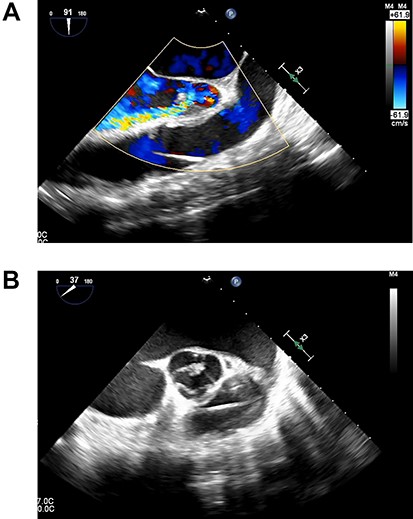

A 33-year-old man with familial dilated cardiomyopathy was urgently admitted to our hospital due to acute decompensation of heart failure with brain natriuretic peptide of 1124.5 pg/ml. Transthoracic echocardiography (TEE) showed left ventricular diastolic diameter of 75 mm, left ventricular systolic diameter of 71 mm, left ventricular ejection fraction of 20% with diffuse hypokinesis. Despite intensive medical treatment with dobutamine at 4 mcg/kg/min, his hemodynamic status did not improve: blood pressure (BP) of 91/56 (67) mm Hg, pulmonary artery pressure (PAP) of 56/18(34) mm Hg, pulmonary capillary wedge pressure of 36 mm Hg, central venous pressure (CVP) of 16 mm Hg. An Impella 5.0 catheter was emergently implanted via the right femoral artery as bridging therapy. After the initiation of Impella at the maximum flow rate, TEE showed no AI. The patient’s hemodynamic status stabilized with dopamine at 1.5 mcg/kg/min and dobutamine at 4.2 mcg/kg/min: BP of 79/66(70) mm Hg, PAP of 36/19(25) mm Hg, CVP of 9 mm Hg. Fifteen days after Impella insertion, heart transplantation was approved. HeartMate III (Abbott, Plymouth, MN, USA) implantation was performed. Intraoperative TEE detected mild AI before the Impella device was removed, which worsened to moderate AI after removal due to prolapse of noncoronary cusps (Fig. 1). At that time, BP of 107/48(67) mm Hg, PAP of 68/33(48) mm Hg and CVP of 9 mm Hg. After Park’s stitch procedure (central AV closure) was performed, diastolic arterial BP increased, with BP of 86/60(70) mm Hg, PAP of 41/25(30) mm Hg and CVP of 12 mm Hg. However, on postoperative Day 1, TEE showed the coaptation stitch on the right and noncoronary cusps had failed, causing severe AI (Fig. 2A and B). In addition, BP decreased to 84/42(49) mm Hg. Consequently, emergent AV replacement was performed. Five days after AV replacement, the patient was discharged from the intensive care unit without any complications.

Transesophageal echocardiography showing moderate aortic insufficiency (AI) due to prolapse of noncoronary cusps after Impella removal.